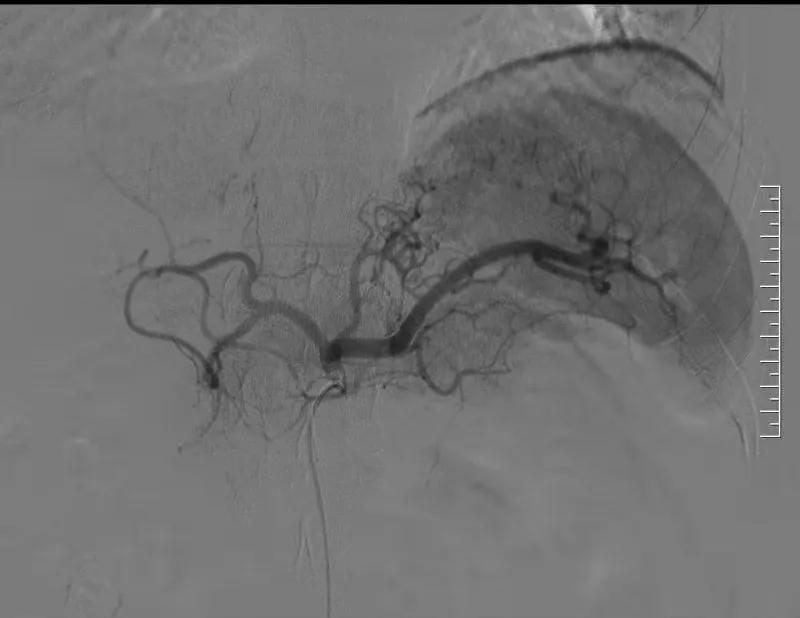

胃左动脉造影显示粗大的胃左动脉,血供丰富